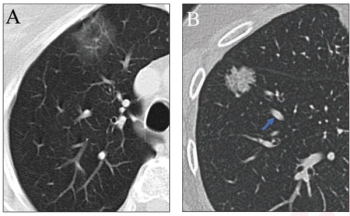

The inclusion of simulated adjudication for resolving discordant nodule classifications in a deep learning model for assessing lung adenocarcinoma on chest CT resulted in a 12 percent increase in sensitivity rate.